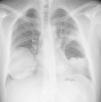

Hidatidosis pulmonar complicada con apertura a vía aérea y cavidad pleural

Complicated pulmonary hydatid cyst with pleural and airway communication